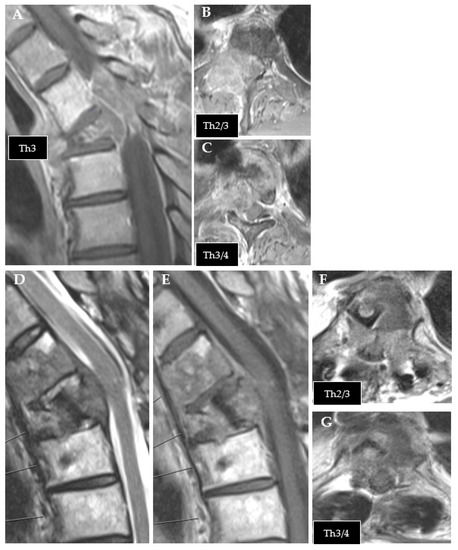

It has been shown in vitro [32] and in vivo [13] that CFR-PEEK reduces artifacts on CT and MR imaging and shows less perturbation effects on radiotherapy dose distributions [15] than titanium, fulfilling the requirements for an optimal application of radiotherapy (Figure 5 and Figure 6) and optimal long-term follow-up imaging. The advantages of CFR-PEEK on follow-up imaging have already been shown in the field of pyogenic spondylodiscitis [33].

Figure 5.

Planning of postoperative radiotherapy: titan. Planning of conventional radiotherapy (30 á 3 Gy) of the vertebral body plus all instrumented levels.

Figure 6.

Planning of postoperative radiotherapy: CFR-PEEK. Less artifacts allow smaller volume radiotherapy of 40/50 Gy á 2/2,5 Gy of the vertebral body alone. Dose escalation is possible and there is less risk to the spinal cord and others structures at risk.